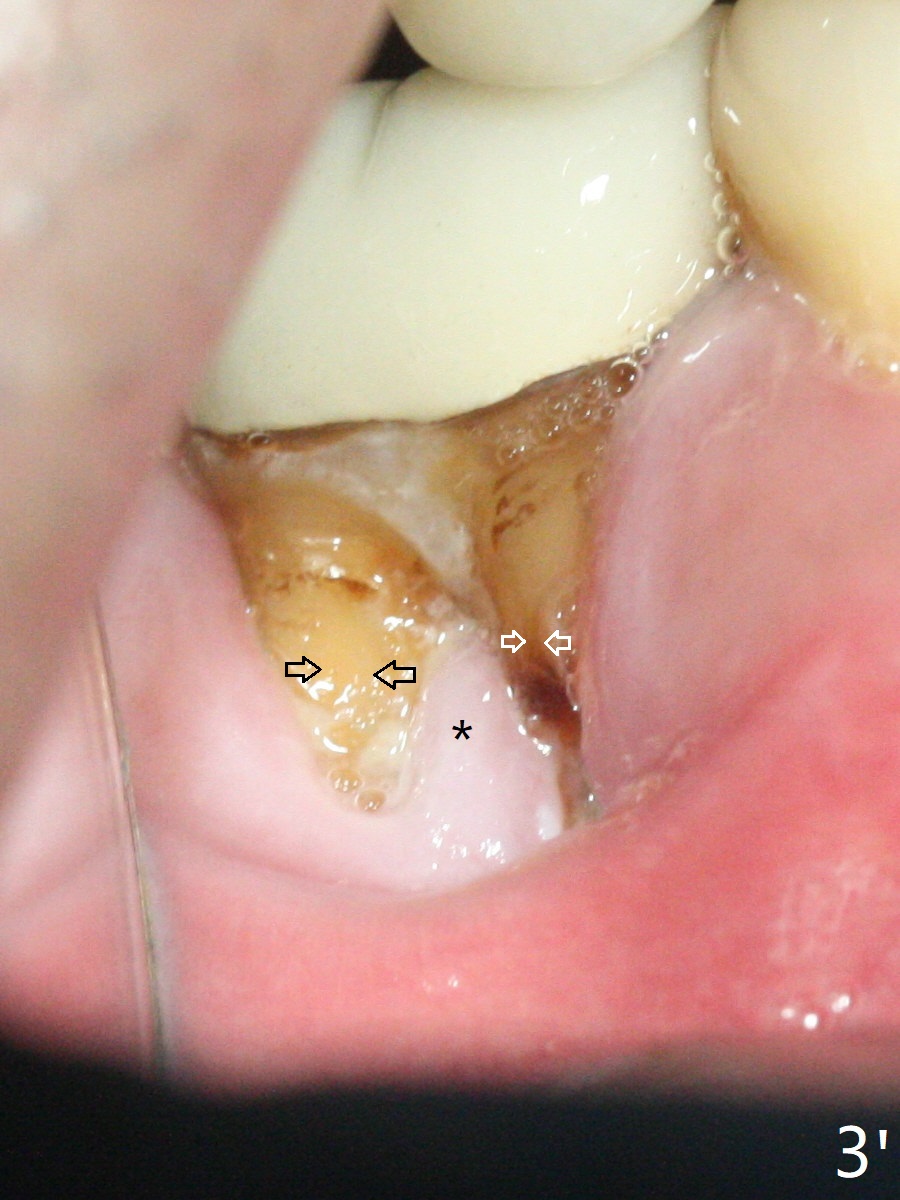

A 47-year-old man has poor dentition. The tooth #31 needs RCT, while #30 has severe PARL, especially mesial (Fig.1 M). The buccal roots are exposed (Fig.2). Between the exposed roots is the septal gingiva, which will be saved for buccal soft tissue repair (Fig.3 *). The septal gingiva will keep in place (not to be transferred) so that the recession will disappear by epithelial regrowth from the nearby gingiva (Fig.3' arrows) over the bone graft and PRF. The provisional should be fabricated to cover the soft tissue defect (Fig.3'' yellow area). In fact the mesial root fractures (Fig.4 ^), as related to the severe bony defect. There seems to be enough lingual bone to hold a 4x13 mm implant (Fig.5 green). Sticky bone (Fig.6 red circles) and PRF (blue) are to be used to repair the hard and soft tissue defects following an immediate provisional (Fig.5,6 yellow outline). Extra layer of acrylic (Fig.6 orange) will be used to cover the PRF buccally. The base of the buccal plate is thick (Fig.6 *); mesial portion appears to be denser (Fig.7 black *) than the distal one (white *). Decortication will be done if hemorrhage is insufficient. Fig.8 is a coronal section of the socket (B: buccal). Extraction (Fig.9 black area) will most likely result in a knife edge ridge. Extraction with bone graft may not fare better, as it is easy to lose the graft considering missing buccal hard and soft tissues.